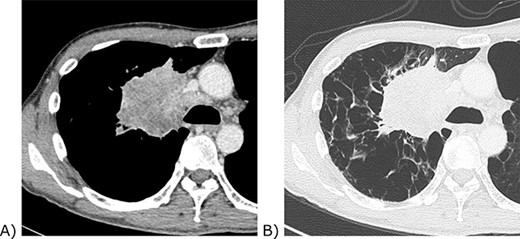

Chest computed tomography of the tumour. (A) Contrast-enhanced mediastinal window view. The tumour invaded the confluence of the superior vena cava and azygos vein. (B) Lung window view. The background lung was emphysematous.